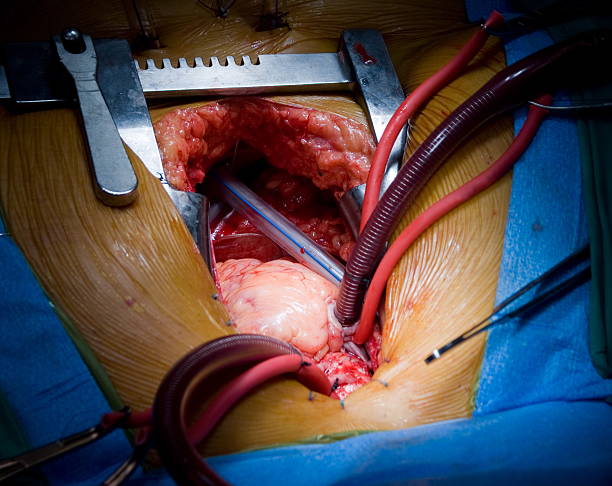

Surgical Management of Intestinal Obstruction

For persistent or severe cases, surgery may be necessary. Surgical management of intestinal obstruction aims to remove the blockage or repair the underlying issue.

- Types of Surgeries:

- Adhesiolysis: Removing scar tissue.

- Resection: Removing a damaged section of the intestine.

- Colostomy/Ileostomy: Creating an opening for waste if part of the bowel is removed.

- Volvulus Repair: Untwisting the affected intestine.